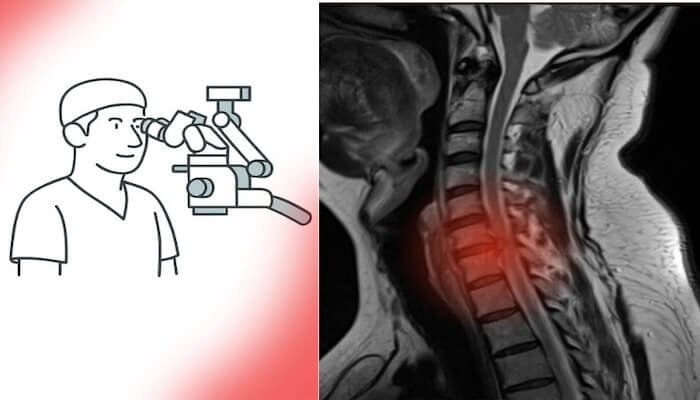

Günümüzde MR ve BT gibi ileri radyolojik görüntüleme yöntemlerine erişim son derece kolaylaştı. Artık neredeyse her şehirde donanımlı hastaneler ve modern tanı merkezleri bulunuyor. Bu sayede en küçük lezyonlar bile erken dönemde saptanabiliyor.

Türkiye’de sağlık hizmetlerine erişim ve radyolojik altyapı son yıllarda ciddi bir ivme kazandı; adeta sağlıkta zirveye ulaşıldı.Bu gelişmeler, tanı sürecini hızlandırarak hem beyin tümörü ameliyatı hem de omurga cerrahisi gerektiren hastaların erken dönemde tespit edilmesini sağladı. Eskiden geç tanı alan birçok vaka, artık uygun zamanda cerrahi müdahaleye yönlendiriliyor. Böylece erken tanı, hem nörolojik kayıpların önlenmesine hem de cerrahi başarı oranlarının artmasına katkı sunuyor.

Beyin ve omurga cerrahisinde son yıllarda yaşanan teknolojik ilerlemeler, cerrahiye bakış açısını tamamen değiştirdi. Artık ameliyatlar daha küçük kesilerle, daha az kan kaybıyla ve çok daha kısa iyileşme süreleriyle gerçekleştirilebiliyor.

Mikrocerrahi, endoskopik cerrahi ve nöronavigasyon sistemleri sayesinde sinir dokuları korunarak işlem yapılabiliyor. Bu da hem cerrahi güvenliği artırıyor hem de genç hastaların ameliyat kararını kolaylaştırıyor.

Eskiden korkulan “uzun iyileşme süresi” veya “kalıcı hasar riski” gibi endişeler, yerini yüksek başarı oranlarına ve hızlı dönüş sürecine bıraktı. Özellikle bel fıtığı ameliyatı, boyun fıtığı ameliyatı ve beyin tümörü ameliyatı gibi operasyonlar artık minimal invaziv yöntemlerle çok daha kısa sürede tamamlanabiliyor.